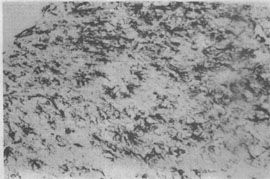

(1)星形胶质细胞增生:常见的致病原因如缺氧、低血糖、感染、中毒等均能引起脑组织的损伤而导致星形胶质细胞增生。反应性星形胶质细胞增生是脑组织损伤的修补愈合反应,主要表现为纤维型星形胶质细胞增生,最后成为胶质瘢痕,胶质纤维酸性蛋白(GFAP)染色呈强阳性(图16-4)。胶质瘢痕与纤维瘢痕不同之处在于星形胶质细胞并不产生胶原纤维及相应间质蛋白。胶持瘢痕是由星形胶质细胞突起构成,其机械强度不如胶原瘢痕。

图16-4 反应性星形胶质细胞增生(GFAP染色)

左上角为脑毁损病灶